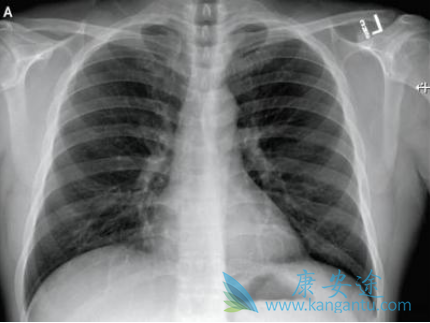

2月2日国家药监局药品审评中心透露,美国吉利德公司(Gilead)在研药物瑞德西韦(Remdesivir)治疗新型冠状病毒感染的肺炎的临床试验申请获国家药监局受理。该药将在武汉开展瑞德西韦的临床研究。该研究或在4月底结束,若药物安全有效,有望获批用于临床使用。

从目前情况看,瑞德西韦被认为存在治疗新型冠状病毒感染的肺炎的可能性,其安全性和有效性仍然有待考证。境外患者使用瑞德西韦治疗有效属于个案。那么瑞德西韦究竟有望何时能获批上市呢?